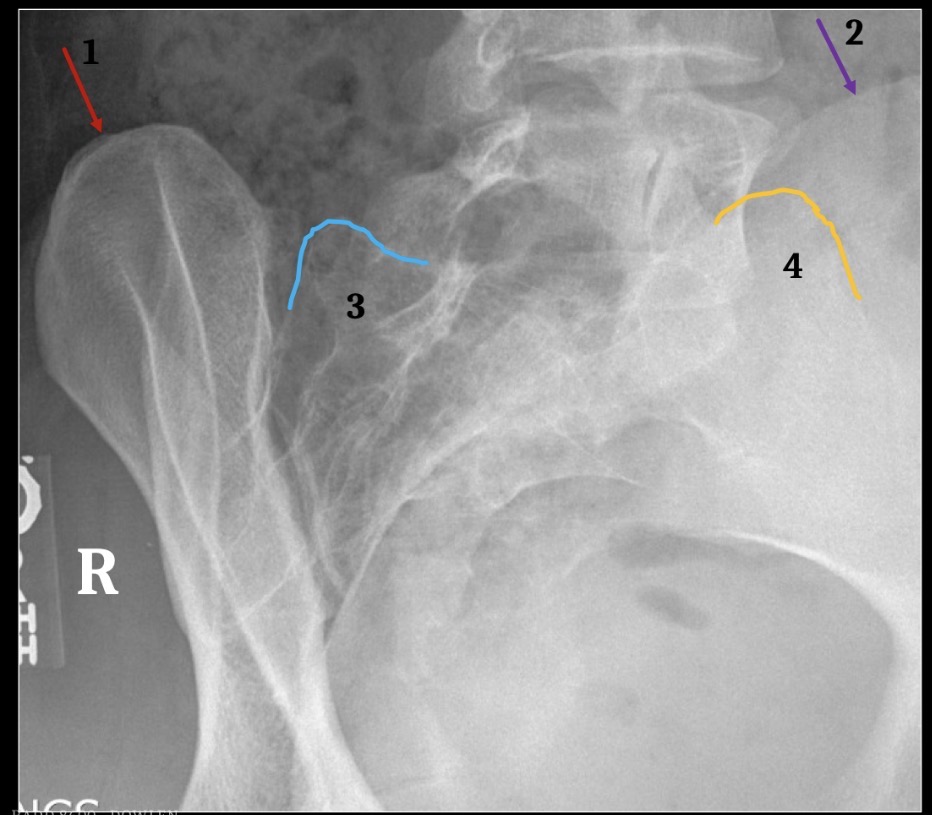

1

T12-L1 intervertebral foramen

2

Rib 12

3

Inferior articular process L2

6

Greater sciatic notch

5

Sacral canal

8

Sacral promontory

9

Iliac crest (2)

11

Transverse process L4

10

Superior articular process L5

12

Anterior body margin of L4

14

Anteriorsuperior body corner L3

15

Intervertebral disc space L1-2